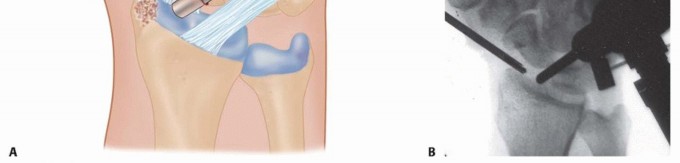

Image

With the joint exposed, the precise location of the impingement is visually confirmed by taking the wrist through a range of motion, particularly radial deviation and extension. The osteotomy is then performed. A micro-sagittal saw or a sharp, thin osteotome is utilized. The cut is initiated on the lateral extra-articular cortex, no more than 3 to 4 millimeters proximal to the tip of the styloid. The blade is directed obliquely, aiming distally and ulnarly to exit precisely at the junction of the styloid and the scaphoid fossa. During the osteotomy, a Freer elevator or a small Hohmann retractor is placed intra-articularly to protect the articular cartilage of the scaphoid from iatrogenic injury.